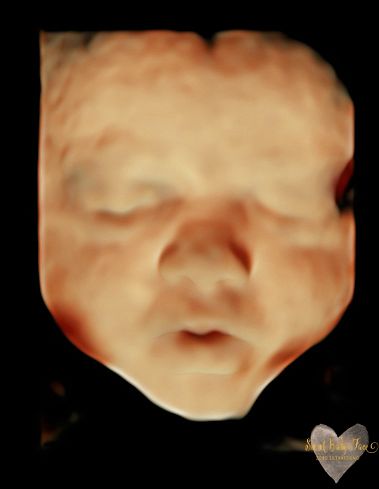

3D/4D/5D Ultrasound Gallery

Take a peek at our Photo Gallery. All of our 2D, 3D, 4D, HD elective ultrasound images are truly ours. They come directly off our machine from our highly trained staff. We can start getting great 3D/4D images as early as 10 weeks!